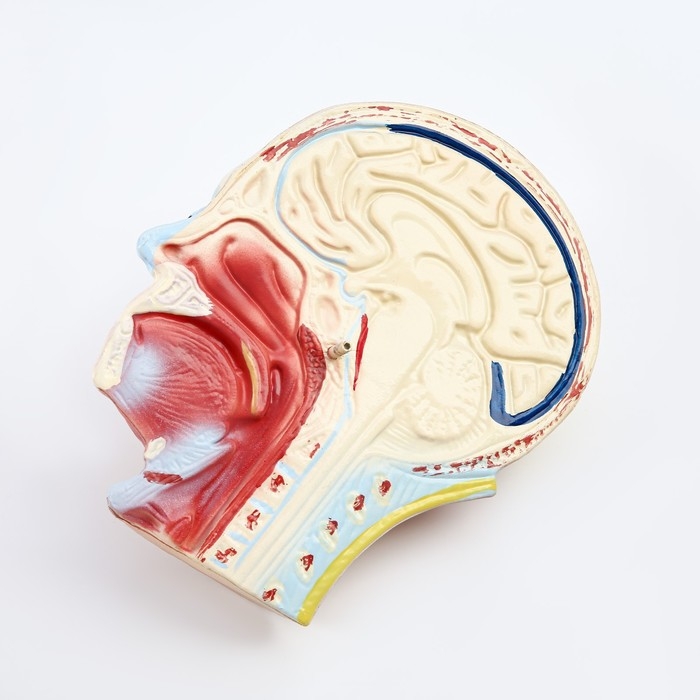

Анатомические модели

ЕКБ 41

No Brand, артикул: 7072360